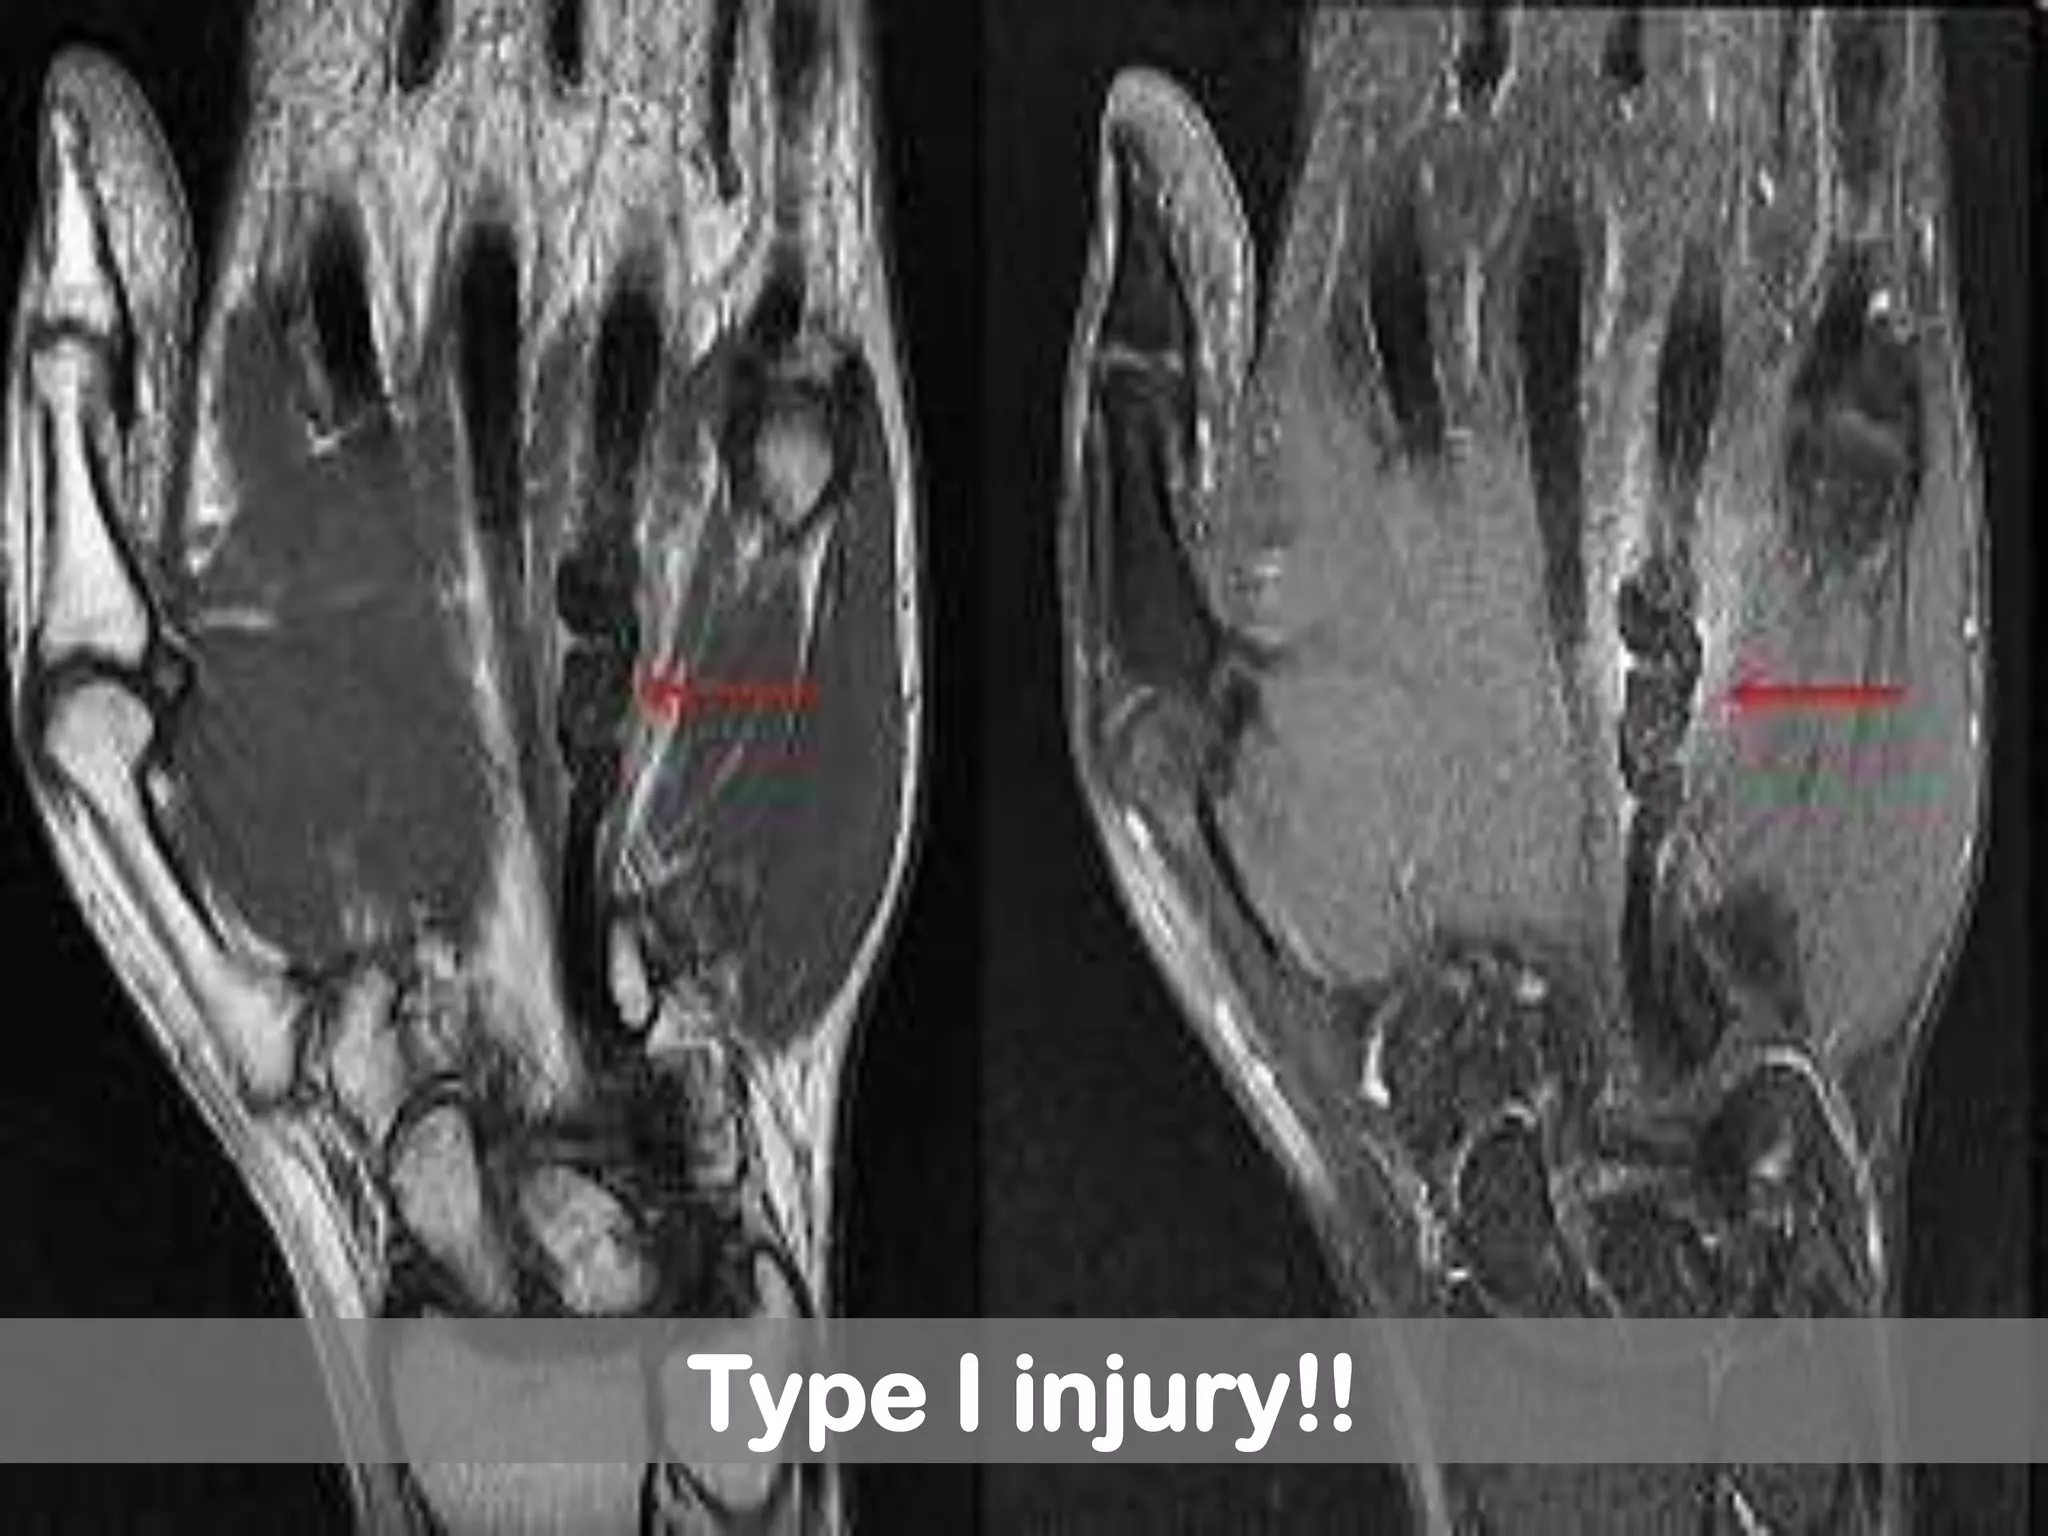

Leddy classification of zone I flexor

tendon injuries!!

Type I: tendon retracted into palm

(fullness in palm)

Type I injury!!